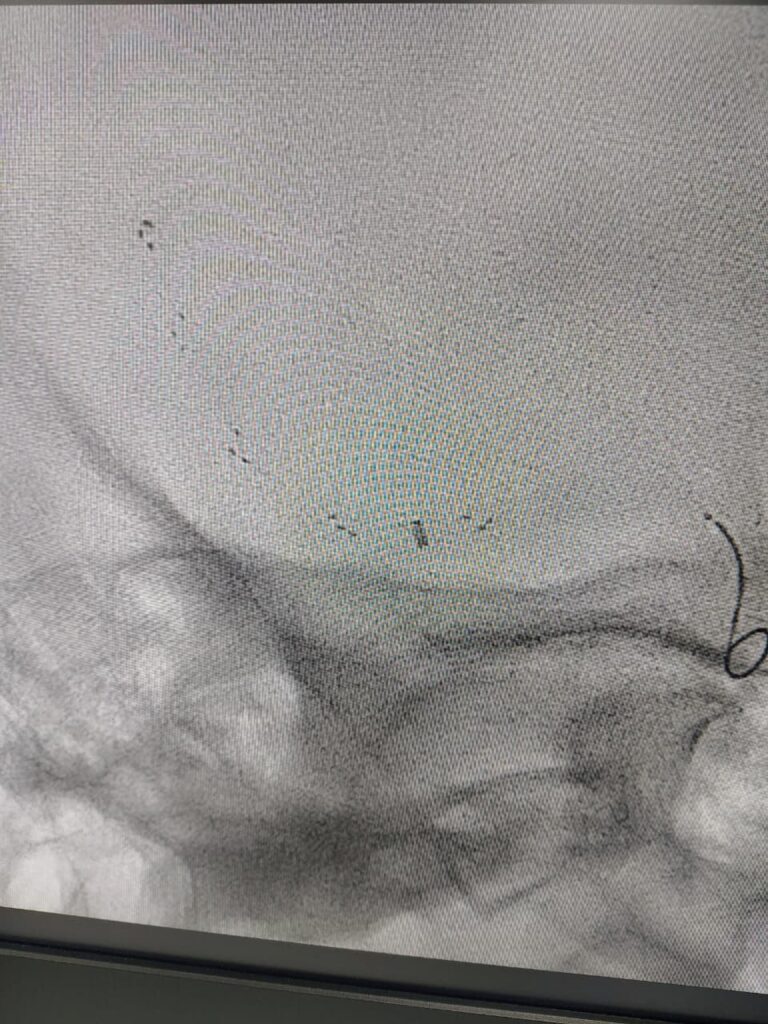

Case 1

A minimally invasive procedure to remove a blood clot from the brain’s blood vessels, restoring blood flow and reducing long-term disability after an acute stroke.